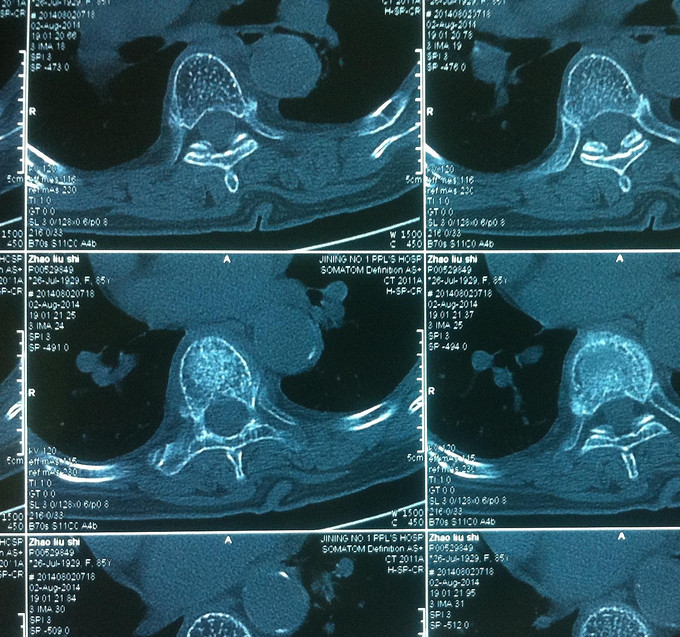

专科查体:背部后凸畸形,背部叩痛,腰骶部无叩痛,双下肢感觉无减退,双下肢肌力4-5级,双侧膝腱反射++,巴氏征阴性。影像学检查:X-Ray;骨质疏松、胸8楔形变。MR:胸8压缩性骨折,新鲜。